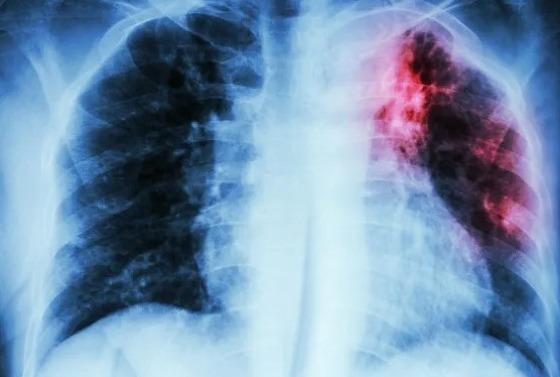

– A doença afeta prioritariamente os pulmões (forma pulmonar);

– Diagnóstico: feito através de teste rápido molecular, exame de cultura e teste de sensibilidade aos fármacos. A realização de uma radiografia do tórax também é indicada;